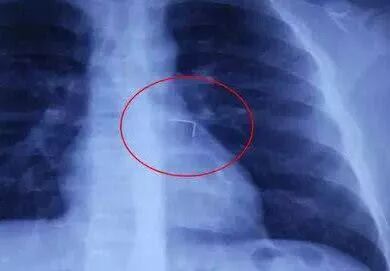

去年,河南14岁的男孩小宇(化名),在嘴里含着圆规针,和同学打闹时,不慎吞下了针。怕被父母责骂,他没敢说出这件事,在恐惧中挨过了4天。后来,因为其他的事,小宇又被妈妈批评了。再也不堪压力的他,大哭着说自己吞了圆规针,让全家大惊失色。那时,圆规针已经生锈了,扎进他的肺粘膜,且针尖离心脏大血管仅仅几个毫米!这几天,孩子明知身处险境,就因怕爸妈发火而不敢求援,该有多煎熬?再多忍一天,估计命儿都没了!我小时候就这样,自己出门摔破了膝盖,沙子和着血肉。回家却不敢说,一个人捂着伤口坐在沙发上发抖。我初中时有个同学就因为不小心弄丢了一两百块钱,她妈就不准她回家,还说回家就拿菜刀砍死她。当孩子犯错惹祸时、遇到难题时,不管有意无意,我们的第一反应,都将影响着孩子的心灵成长。